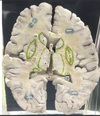

1. At what level through the cerebrum is this section taken? 2. Identify the specific structure labelled 1. 3. Identify the structure labelled 2. 4. Identify the structure labelled 5. 5. Identify the specific structure labelled 8. 6. Identify the structure labelled 10.

1. The level of interventricular foramen 2. Genu of Corpus Callosum 3. Septum Pellucidum 4. Column of Fornix 5. Spleenium of Corpus callosum 6 Crus of Fornix

1. Identify the specific structure labelled 3. 2. Identify one afferent fiber of this structure. 3. Identify one efferent fiber of this structure.

Caudate Nucleus Cortico striate, thalamo striate, nigro striate , Striato pallidal , Striato nigral

1. Identify the specific space labelled 4 2. Give its developmental origin.

Anterior horn of lateral Ventricle Central Canal of neural tube

1. Identify the structure labelled 6.

thalamus

1. Identify the structure labelled 7. 2. Give its subdivisions. 3. Give its afferent fibers. 4. Give its efferent fibers.

1. Lentiform Nucleus 2. Putamen, globus pallidus externas, globus pallidus internus 3. Corticostriatal, nigrastriatal 4. striatonigral, striatalpallidal

1. Identify the structure labelled 9. 2. Identify the structure labelled 11. 3. Identify the vessels lining the structure labelled 11.

1. Tail of caudate nucleus (goes to amygdala) 2. Insular cortex 3. short perforator branches from the superior division of the middle cerebral artery (MCA)

1. Identify the structure labelled 12 2. What type of meninges covers this structure? 3. What is the main function of this structure? 4. In which ventricular structures is this structure present? 5. In which ventricular structures is this structure absent?

1. Choroid Plexus 2. Pia Mater 3. Produces SF in ventricles of brain 4. Lateral 5. cerebral aqueduct, frontal horn of the lateral ventricle, [1] and occipital horn of the lateral ventricle

1. Identify the specific structure labelled 13. 2. What fibers can be found in this structure?

1. Posterior Limb of Internal Capsule 2. Corticospinal Fibres

1. Identify the specific structure labelled 14. 2. What fibers can be found in this structure?

1. Anterior Limb of internal capsule 2. Frontopontine, thalamocortical